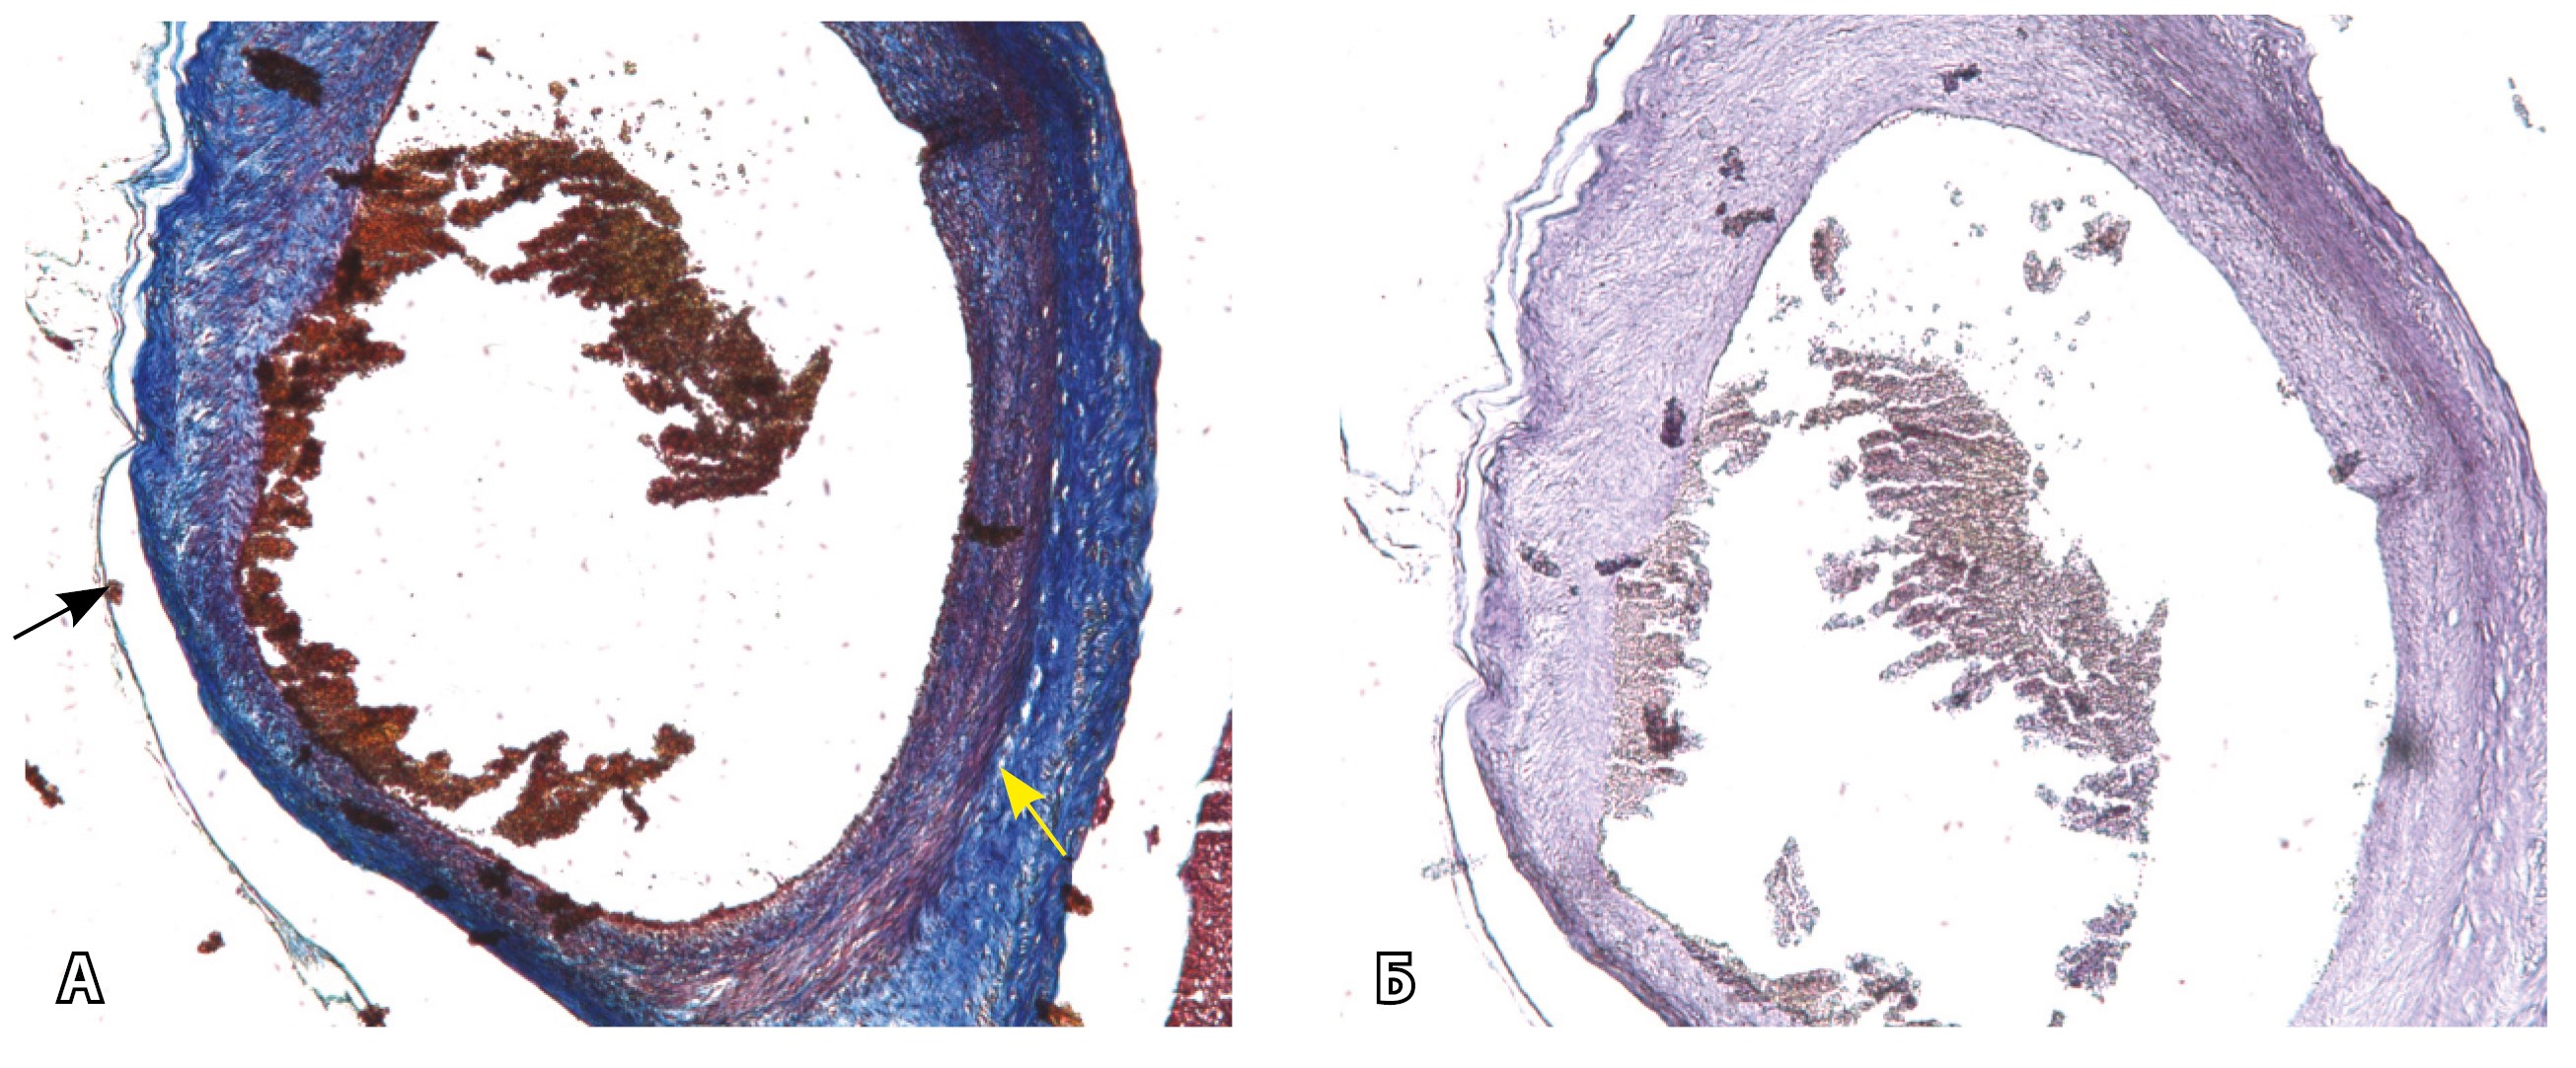

На микропрепаратах васкуляризация серозной оболочки представлена множеством крупных сосудов, идущих в разных направлениях и анастомозирующих друг с другом. Возможно, имеются артериовенозные соустья. На серийных срезах также видно, что в стенках артерий трудно различимы два слоя миоцитов (продольный и поперечный). Со стороны адвентиции они окружены толстым «футляром» из грубоволокнистой голубой ткани (при окраске по Маллори). Она проникает в стенку артерий, замещая мышечный слой (рис. 12).

Рис. 12. Истончение миометрия; в составе серозной оболочки видна крупная артерия, окруженная плотной соединительной тканью. А – cосуды в составе серозной оболочки (окраска по Маллори; × 200), не дифференцированная на мышечные оболочки стенка артерии, справа – вена, оба сосуда покрыты фиброзной оболочкой, внизу виден слой мезотелия в составе серозной оболочки; Б – серийный срез тех же сосудов при окраске на выявление эластических волокон, сосуд с соединительнотканной муфтой (окраска по Вейгерту; × 50): определяется полная дезорганизация эластичного материала в стенке; стрелкой указан мезотелий (аналог pl. increta, PAS 2 по FIGO)

Эластический каркас представлен сетью тонких волокон, без концентрации на внутреннюю и внешнюю мембраны. Однако маркер СD34 констатирует сохранение эндотелия, что свидетельствует о том, что по артериям циркулирует кровь, не сворачиваясь (рис. 13).

Рис. 13. Самые крупные сосуды в пределах серозной оболочки стенки матки: А, Б – серийные срезы артерии; × 50. При окраске по Маллори (А) видна тонкая полоска мезотелия (черная стрелка), слабо дифференцированная мышечная стенка артерии, вокруг нее – плотная коллагеновая оболочка (желтая стрелка), в просвете определяются тромботические массы. При окраске по Вейгерту (Б) наблюдается полная потеря внутренней и внешней эластических мембран